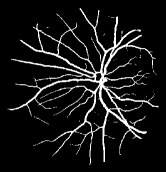

As pointed out in recent works [15, 17], a good semantic segmentation network should learn multi-level features. Further, it should have multiple stages with different receptive fields to learn more inherent features from different scales. FCN, taken as an example, uses skip connections to fuse multiple stages outputs, as well as the HED network, in which a series of side-output layers are added after each stage in VGGNet. The HED network was first proposed for edge detection, and further used for image-level vessel segmentation in recent studies [6, 16], with significant performance. However, our experimental results show that such network architecture is not appropriate for vessel segmentation directly. Figure 1 provides such an illustration. Reasons for this phenomenon are straightforward. On one hand, the side-output of the first layer often contains too many noises. On the other hand, the features produced by the last side-output layer are too coarse due to information loss of pooling operation. Obviously, the inaccurate vessel map of side-output1 and side-output4 should have negative impacts on the final segmentation result.

2.2 Bottom-top short connections

With the deepening of DSN network, the receptive field of each side-output layer gets larger, which makes the corresponding vessel map much blurrier as observed from the first row in Figure 1, especially for side-output4. These observations inspired us to pass low level fine semantic information to high levels to alleviate the blurring situation.

Bottom-top short connections aim to refine high-level segmentation results. However, we can observe from the first two rows in Figure 1 that the vessel map generated by the first side-output layer contains too many noises while the map generated by the last side-output could capture the main vessel structure. Therefore, we propose delivering high-level structural information to the first side-output layer to reduce its noises. We implemented this kind of information delivery by a top-bottom short connection from conv4 to feat_conv1, which can been seen in Figure 4. We first convolved the last convolution of conv4 using 1 convolution kernels with size 33. Then the obtained feature map are up-sampled 8 to get feat_4_1. The information (feat_4_1) passed from conv4 are concatenated with feat_conv1 to form feat_conv1_fuse (see Figure 5). At last, one hand hand, we perform a 11 convolution operation on feat_conv1_fuse to get the information (feat_1_2) delivered to feat_conv2. On the other hand, we performed convolution operation with a kernel size of 11 and sigmoid transformation for feat_conv1_fuse sequentially to obtain the segmentation result (side 1). At last, side 1 is compared with the ground truth to get the loss of the first side-output layer.

In addition, we can observe from Figure 1 that the side-output1 and side-output4 of the BTS-DSN were more accurate compared with those of the DSN.